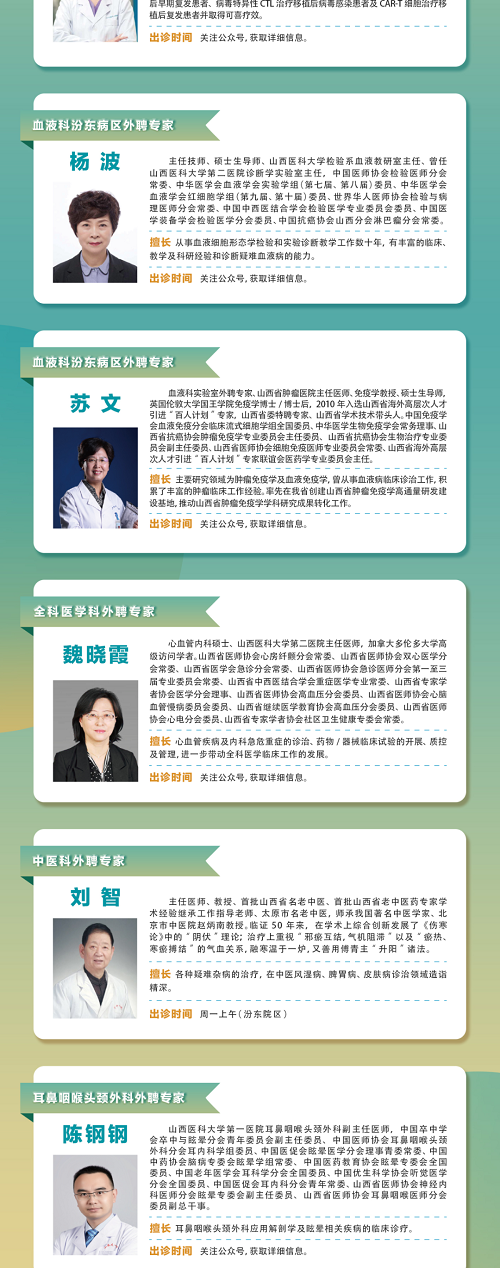

學科帶頭人

林樹忠

骨科汾東三病區主任、副主任醫師、碩士、運動醫學專業學組組長、骨關節疾病專家。

擅長四肢關節運動損傷的微創治療,如半月板成形、韌帶修補、軟骨移植、前后交叉韌帶重建、肩袖損傷修補、髖關節撞擊綜合征、踝關節撞擊綜合征、滑膜皺襞綜合征等微創手術治療;輕中度膝關節骨性關節炎的保膝治療,重度髖膝骨性關節的人工關節置換治療。

聯系電話:13503509864

專家門診

林樹忠副主任醫師:周一、周四上午

普通門診

何君仁主治醫師門診:周三上午、周五下午

劉文琦主治醫師門診:周二下午

杜晉強主治醫師門診:周四下午

咨詢電話

0351-5656547

門診地址

府城院區

太原市中心醫院府城院區:山西省太原市杏花嶺區解放路東三道巷1號。

交通指南:乘坐25路、3路、615路公交車至北肖墻壩陵北街口(征兵大廈),向西100米;乘坐610路(臨)、820路、820支路(臨)、829路(臨)公交車至解放路市中心醫院站,東二道巷向東200米即到。

汾東院區

太原市中心醫院汾東院區:山西省太原市小店區汾東大街256號,汾東大街與太茅路交叉路口東南角。

交通指南:乘坐公交車906,306路公交,賈家寨村下車可達。